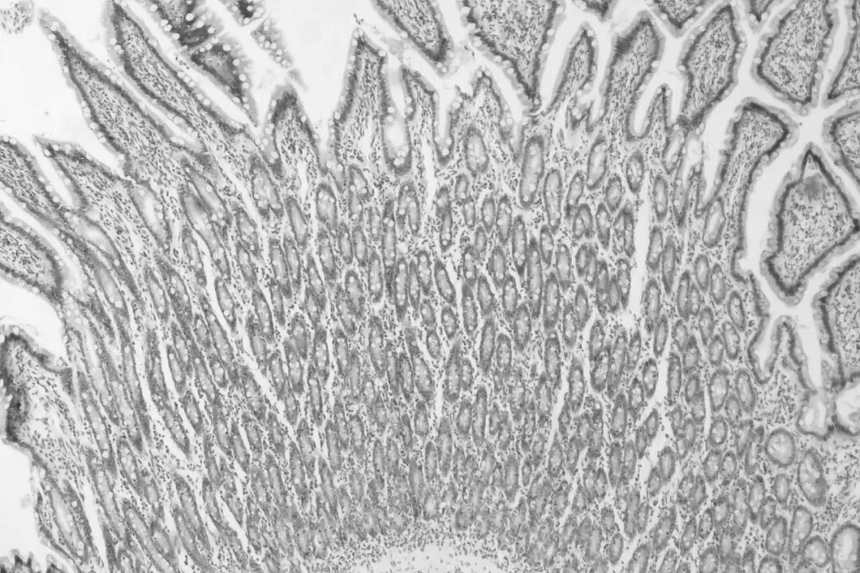

U系列相机具备高灵敏度、高分辨率等性能特点每个像素都能够准确地捕捉并呈现实际场景中的细微特征从微小的零件到微观的纹理,所有的细节都非常清晰可辨。图像边缘和边界线条清晰,色彩饱满且准确。